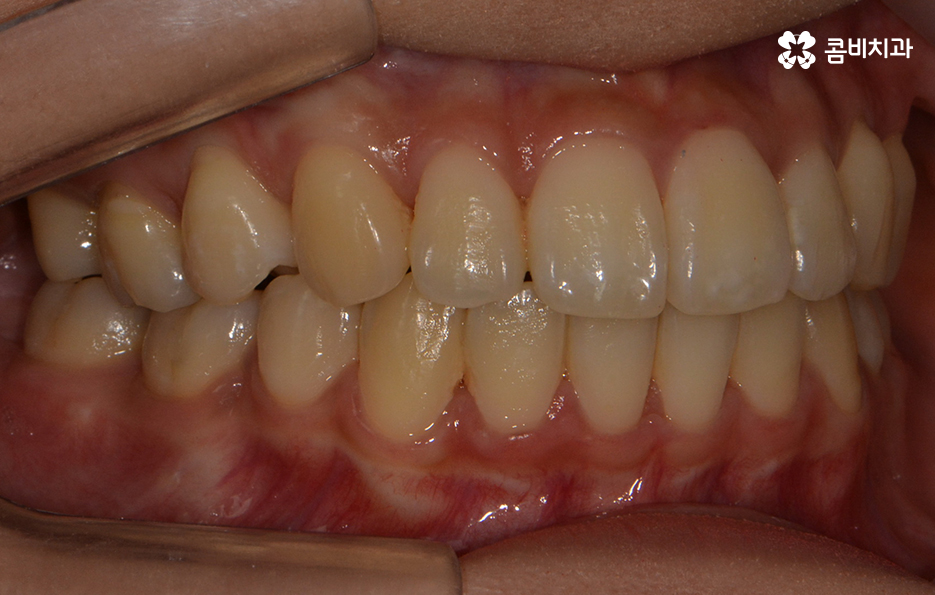

초기에 시술이 진행된 모습에 비해서 윗니가 가지런해졌고

돌출되었던 치아가 안쪽으로 많이 들어온 모습입니다.

발치를 했던 부위가 어딘지 잘 모를 정도로

윗니가 안쪽으로 들어와서 가지런하게

치열이 자리 잡고 있는 모습입니다.